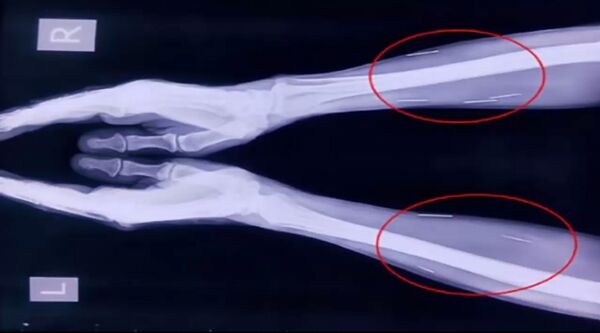

Reprenons cette histoire incroyable depuis le début. Badrilal Meena, un Indien de 56 ans, se plaignait de fortes douleurs à l'orteil. Afin de mesurer l'ampleur du problème, les médecins l'ont envoyé faire une radio. Quel ne fut pas leur étonnement en découvrant une trentaine d'aiguilles piégées sous sa peau et dans ses muscles.

Mais c'était seulement la première surprise: les médecins ont ensuite procédé à des radios du reste du corps et ont découvert encore une quarantaine d'aiguilles dans la gorge de leur patient. Au total, le corps de M. Meena en contenait 75.